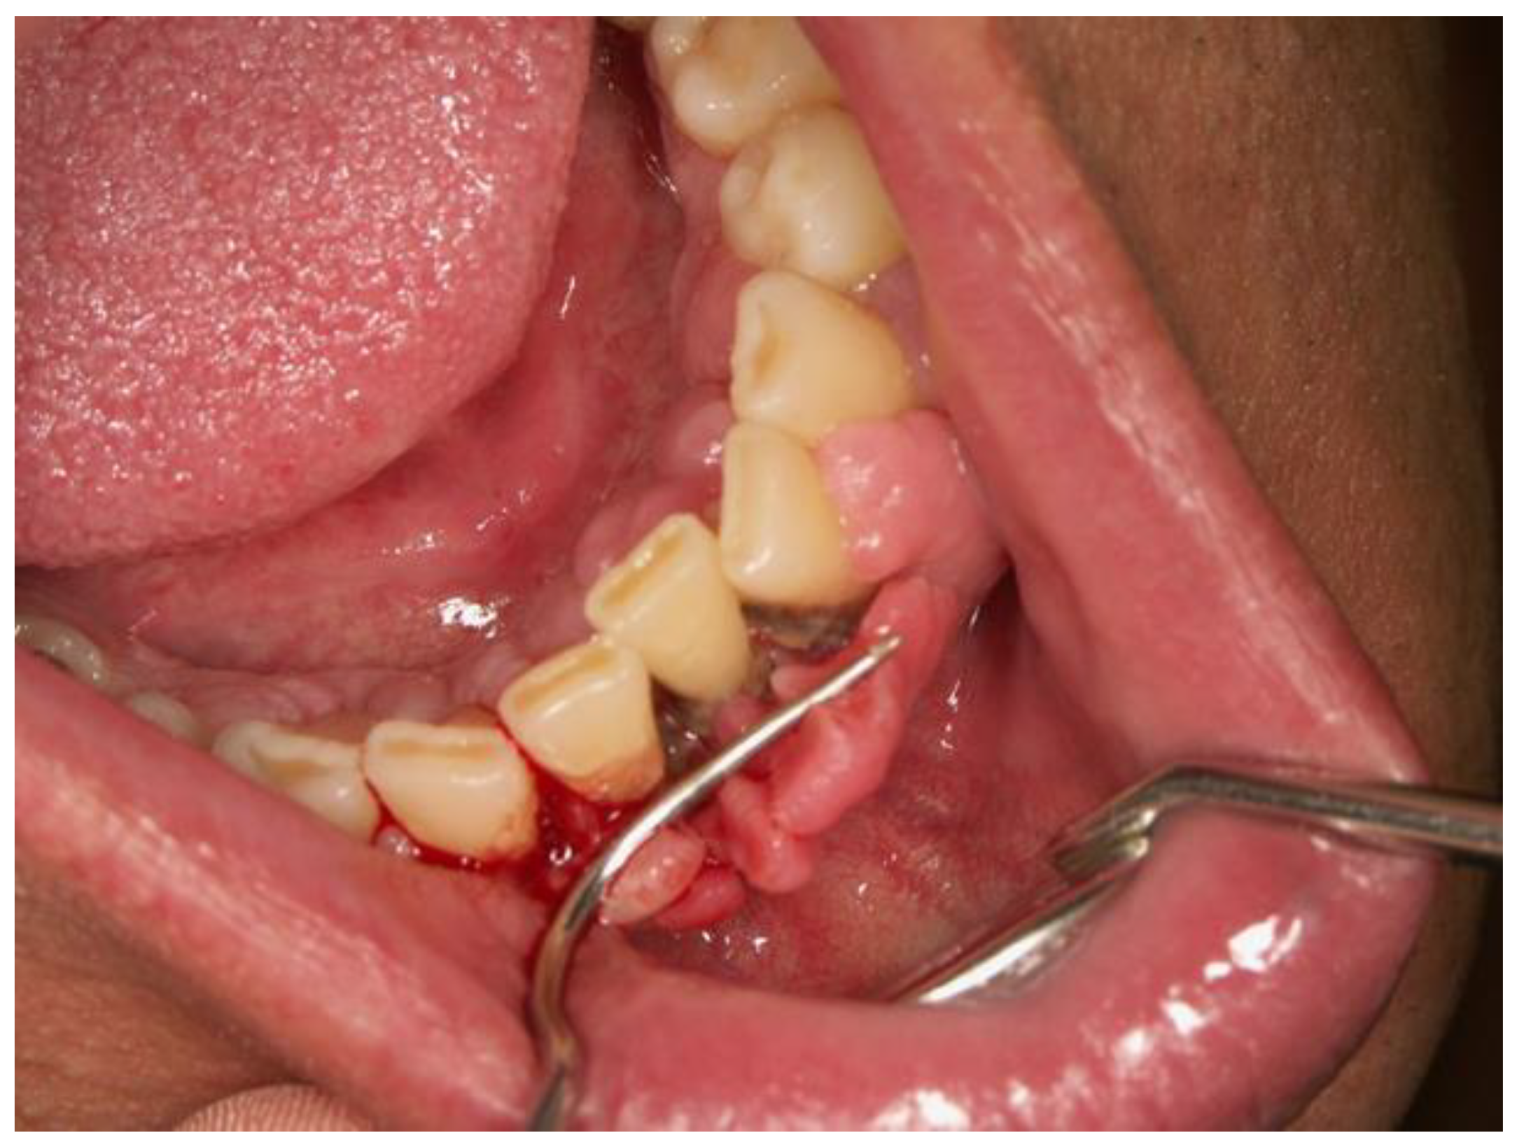

Oral Manifestations of Vitamin C Deficiency